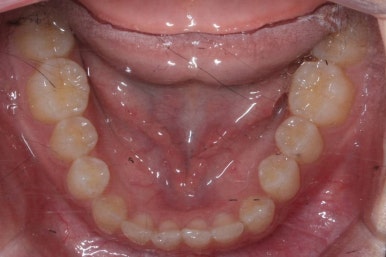

마무리 때의 사진입니다.

윗니만 부분교정하였지만 교합에도 이상 없이 매복되었던 송곳니는 매우 잘 위치를 잡았습니다.

송곳니 부위는 다시 틀어지지 않게 하기 위해 유지철사를 붙여주었습니다.

총 치료기간은 20개월 소요 되었습니다.

부산매복치아교정 상악 부분교정을 통해 매복치를 교정해준 이번 치료의 전후사진 비교입니다.

썩은 유치 대신 영구치 송곳니는 매우 자연스럽게 위치되었습니다. 아랫니는 교정하지 않았기 때문에 약간 삐뚠 느낌은 남아있지만 맞물림은 크게 문제가 없게 마무리 되었습니다.